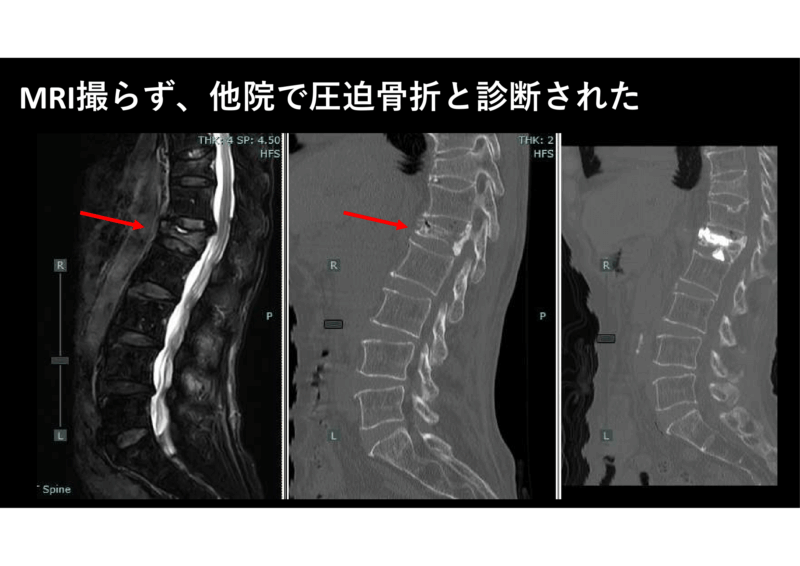

淡海せぼねクリニックではMRIの適応についてできるだけ丁寧にご説明しています。上に書いたような事情も混ぜて伝えています。腰椎MRIでは特に急性発症例では圧迫骨折を疑いますのでできるだけ撮ります。私は腰痛をこう診ている 「急ぐか、MRI要るか」 | 淡海せぼねクリニックブログ

1年半前に「初診月のMRIは原則認定しない」と国保連合にはっきりと言われ、その直後に腰痛患者AさんのMRIをある先生が撮りませんでした。国保連合のセオリー通りです。私であれば、なんとなくそのあとの事態を予想して「国が認めんでも良い」としてMRIを撮ったと思います。Aさんは数日後に救急で医療センターに搬送され、入院されました。のちにAさんの娘にどえらい電話で怒られました。「圧迫骨折だった」と。幸いに3か月後に受診してくれましたので、MRIなどすべて行い、話し合いの末にBKP手術を行いました。

時間がたっていたのですが、ラッキーなことに症状は改善され、今でも外来に通院してくれています。いつもこの患者さんのことを思い出しますので、特に腰痛の患者さんでは適応を広げて、7割査定されてもMRIを撮ります。他院でせぼねの病気が見つかったら恥ずかしいですから。